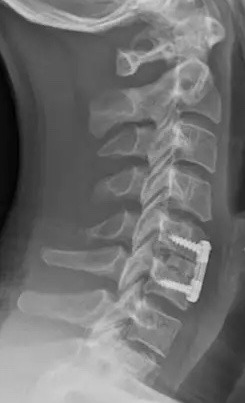

Gallery

Explore our advanced spine care visuals.